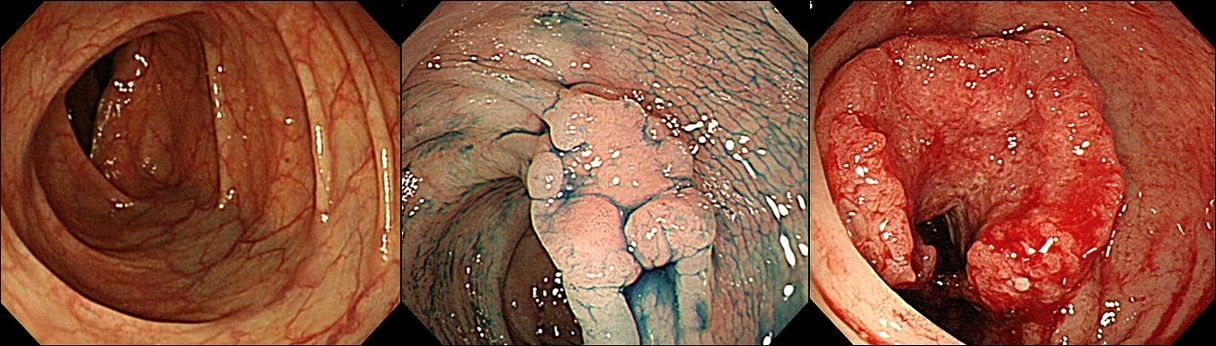

(왼쪽부터) 정상 대장 점막, 조기 대장암, 진행성 대장암 모습. 사진 서울아산병원